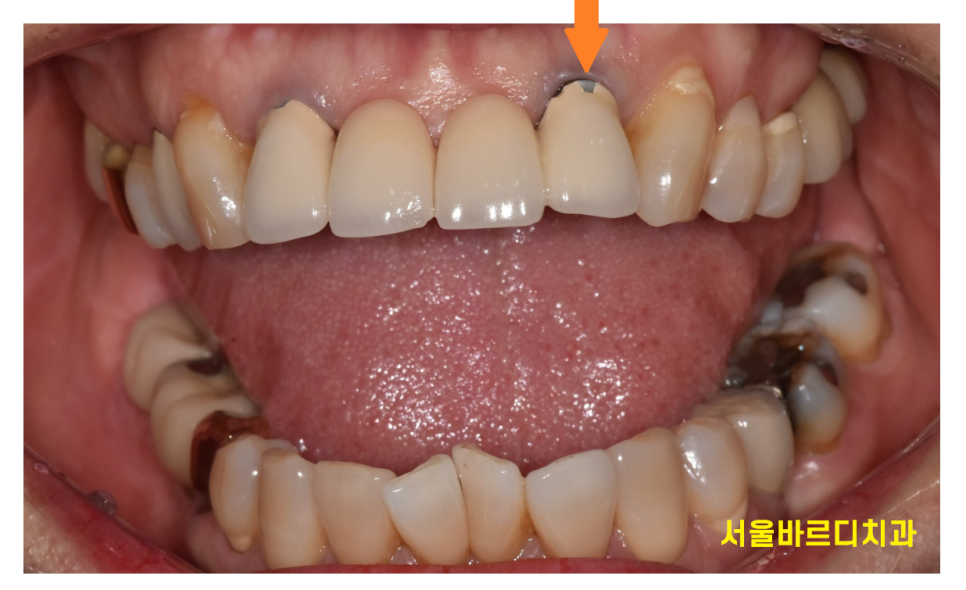

보철을 제거해보았습니다.

240701

역시나 하신지 10년이 넘었고

치아를 보강했던 흔적이 있던만큼

내부 상태가 좋지 않았습니다.

내부가 다 삭아있었는데요.

이대로 치료를 하게되면

오래 못쓸것이 분명하여 발치 후

송곳니부터 송곳니까지

6개의 치아를 걸어 치료하기로 하였습니다.